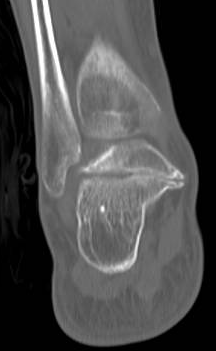

跟骨-足舟骨联合的骨化常常发生在8至12岁,而跟骨-距骨联合的骨化常常发生在12至16岁,开头所说的姚阿姨便是属于跟骨-距骨联合,也就是说姚阿姨可能在青少年的时候就已经出现了跗骨联合。并非所有的跗骨联合都会产生症状,且由于过去经济条件及对此病认识的不足,姚阿姨并没有重视,随着年龄增大,距下关节软骨退变逐渐加重,经过这一次扭伤才意外发现了此病。

箭头所示为跟距联合。